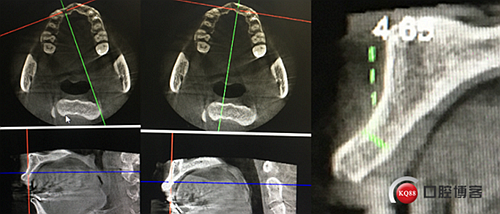

“以修復(fù)為導(dǎo)向”,在前牙種植體中心點(diǎn)就是未來牙冠舌側(cè)窩位置。那這個(gè)病例植體的方向和位置就只能是下圖右側(cè)這樣了。很明顯植體根尖部分要穿出唇側(cè)倒凹的。怎么辦?翻大瓣植骨蓋膜減張縫合?不!可以不翻瓣,大家仔細(xì)看看下圖右圖我畫的那條細(xì)細(xì)的弧線,是不是跟原來唇側(cè)凹陷的骨面成為左右對(duì)稱的兩條弧,也就是說骨膜從原來唇側(cè)凹陷骨面上剝離然后放到左側(cè)我畫的那條弧線那里根本不需要減張,這兩條弧線之間也就是唇側(cè)凹陷處放上骨粉,骨膜不會(huì)增加張力。不知道大家看明白了沒有。